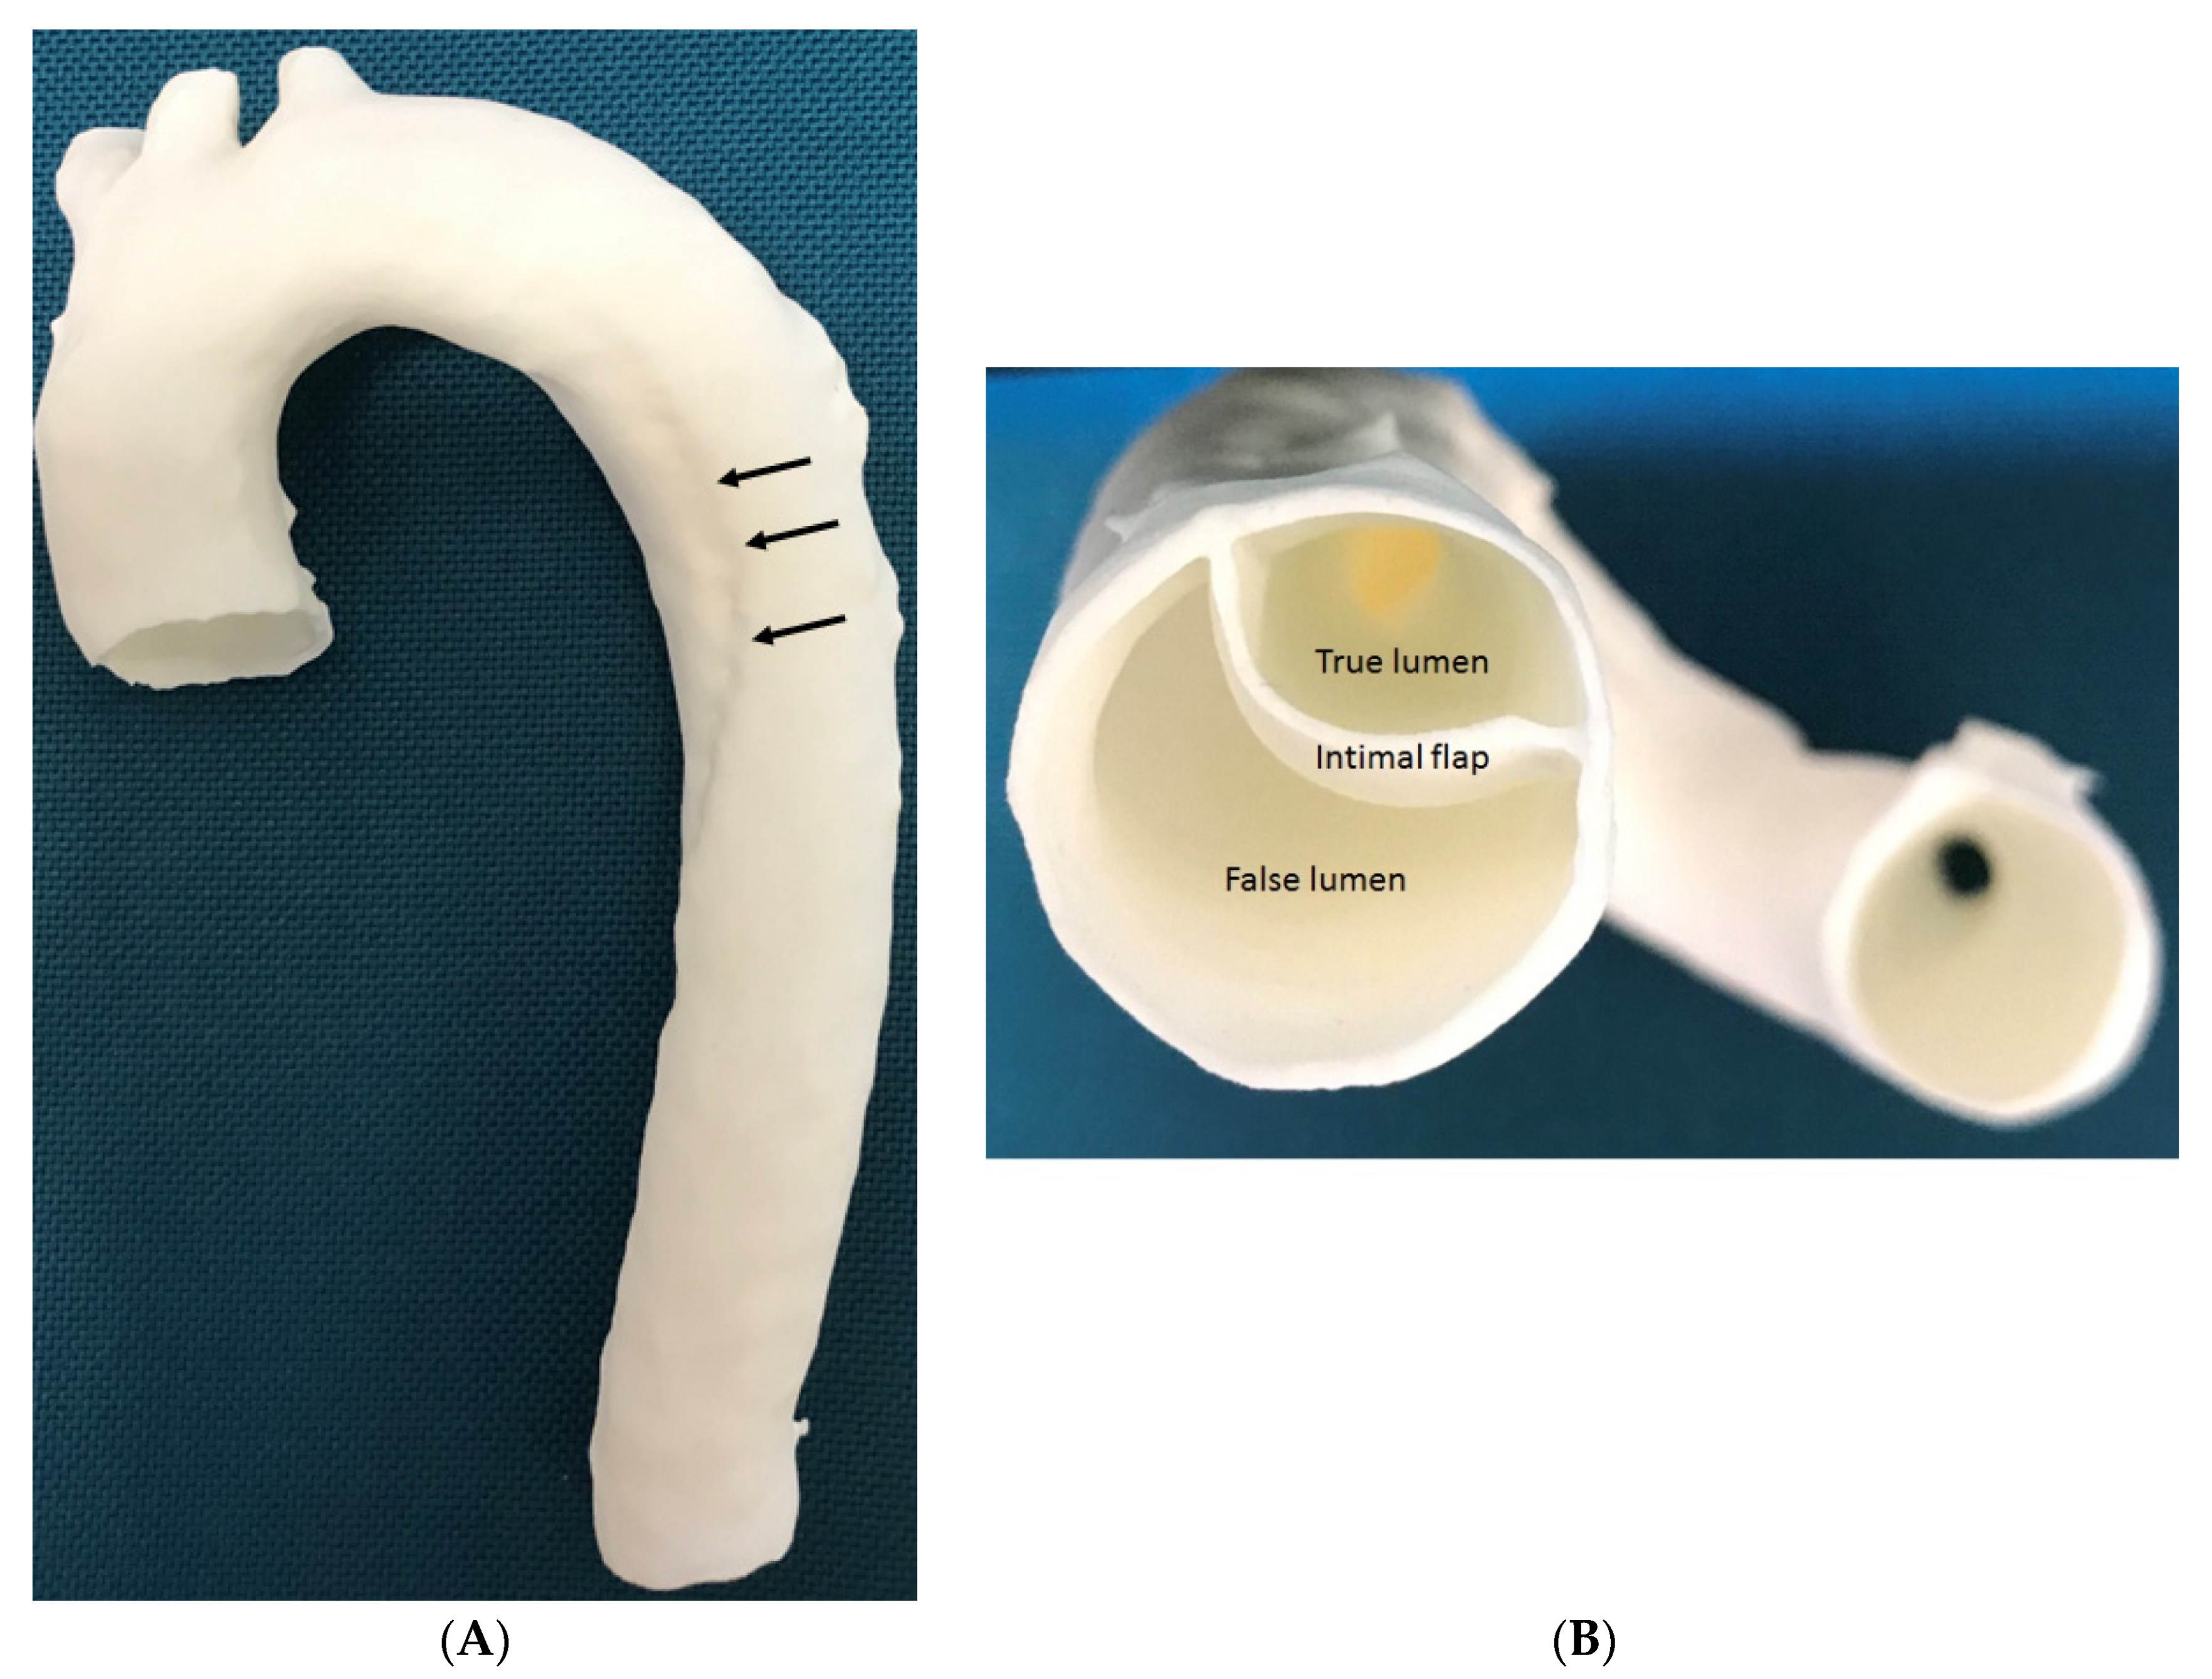

- Ho, D.; Squelch, A.; Sun, Z. Modelling of aortic aneurysm and aortic dissection through 3D printing. J. Med. Radiat. Sci. 2017, 64, 10–17. [Google Scholar] [CrossRef] [PubMed]

- Sun, Z.; Squelch, A. Patient-specific 3D printed models of aortic aneurysm and aortic dissection. J. Med. Imaging Health Inf. 2017, 7, 886–889. [Google Scholar] [CrossRef]

- Hossien, A.; Gesomino, S.; Maessen, J.; Autschbach, R. The interactive use of multi-dimensional modeling and 3D printing in preplanning of type A aortic dissection. J. Card. Surg. 2016, 31, 441–445. [Google Scholar] [CrossRef]